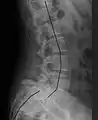

| X-ray of the lateral lumbar spine with a grade III anterolisthesis at the L5-S1 level | |

Spondylolisthesis is graded based upon the degree of slippage of one vertebral body relative to the subsequent adjacent vertebral body.[6] Spondylolisthesis is classified as one of the six major etiologies: degenerative, traumatic, dysplastic, isthmic, pathologic, or post-surgical.[7] Spondylolisthesis most commonly occurs in the lumbar spine, primarily at the L5-S1 level, with the L5 vertebral body anteriorly translating over the S1 vertebral body.[7]

Classification by degree of the slippage, as measured as percentage of the width of the vertebral body:[17] Grade I spondylolisthesis accounts for approximately 75% of all cases.[7]

- Grade III: 50–75%